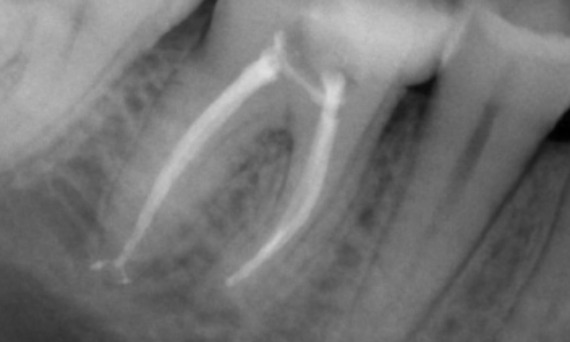

"Ein patienten- und behandlungsorientierter Erfolg." Dr. Cowie

Vorher: Periapikale Radioluzenz primär an der distalen Wurzel und Verlust der Lamina dura an der mesialen Wurzel.

Nachher: In diesem Fall wurde TruNatomy gewählt, um einen kariesfreien Ansatz zu ermöglichen und sich auf den Erhalt des perizervikalen Dentins zu konzentrieren, insbesondere auf der mesialen Seite, wo der Zahn eine minimalere Restauration aufwies.

Bath, UK